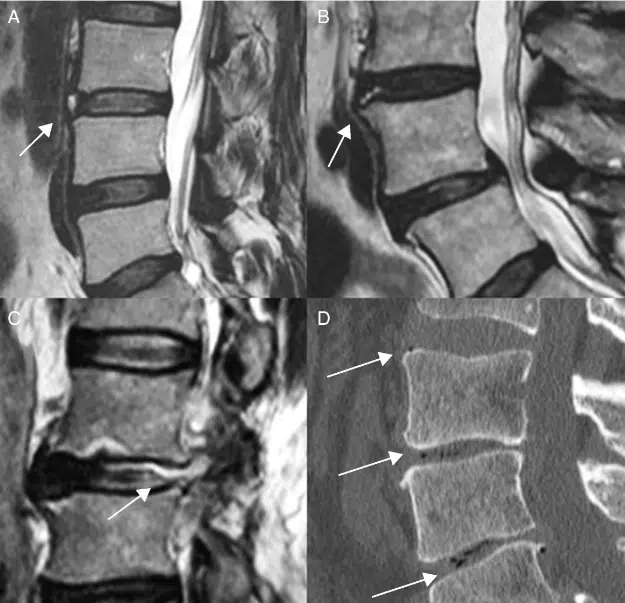

Se hacen pruebas que tratan de exponer los tejidos dañados, provocados por el deslizamiento, se pueden presentar al mismo tiempo una hernia de disco o desgaste de la columna, ya que las cargas son diferentes, por eso se solicitan los estudios de radiografía, a veces se necesitan resonancia magnética o tomografía computarizada.

En la consulta quiropráctica es común encontrar en imágenes de radiografía desplazamientos de las vértebras lumbares en la vista lateral.

Estos estudios se solicitan en los pacientes que presentan dolores que pareciera que perforan la espalda baja, que se recorren a la parte anterior del abdomen en forma de cinturón y que empeora si el paciente se extiende la espalda hacia atrás.